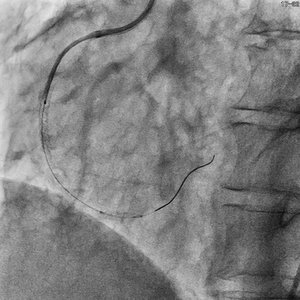

撮影よりも低線量の透視において、更に半分のフレームレートでも十分な視認性を確保している。